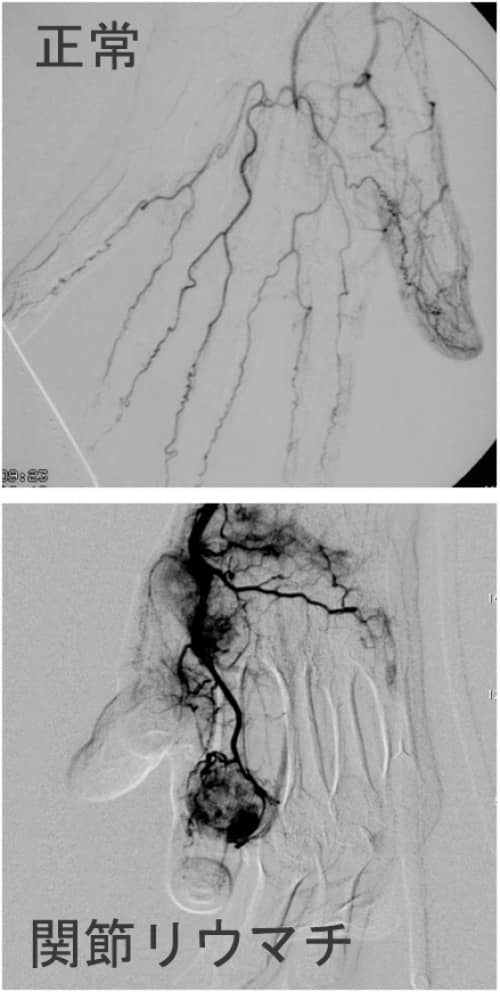

正常な血管と異常な血管とは?

[記事提供:オクノクリニック | モヤモヤ血管による慢性痛治療(https://okuno-y-clinic.com)]…